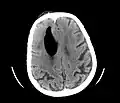

Additional images

Large pneumocephaly secondary to surgical wound

Pneumocephaly